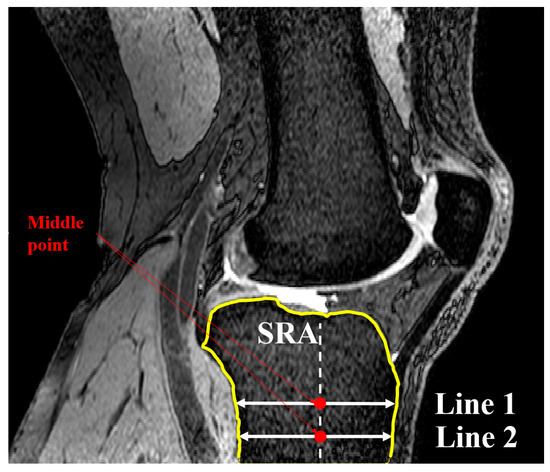

2.3. Concavity Zone

2.1. Medial and Lateral Tibial Slope Measurement Methodology